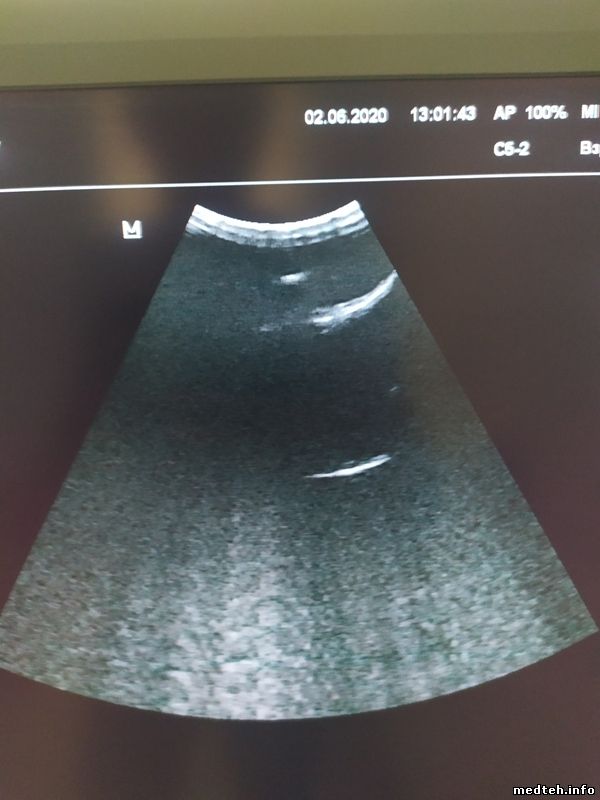

Добрый день.

Имеем филиповский датчик С5-2, аппарат перестал его видеть (на других аппаратах проверяли).

В чём может быть причина, кто сталкивался?

Механически не повреждён.